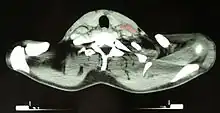

After Hodgkin lymphoma is diagnosed, a person will be staged: that is, they will undergo a series of tests and procedures that will determine what areas of the body are affected. These procedures may include documentation of their histology, a physical examination, blood tests, chest X-ray radiographs, computed tomography (CT)/positron emission tomography (PET)/magnetic resonance imaging (MRI) scans of the chest, abdomen and pelvis, and usually a bone marrow biopsy. PET scan is now used instead of the gallium scan for staging. On the PET scan, sites involved with lymphoma light up very brightly enabling accurate and reproducible imaging.[35] In the past, a lymphangiogram or surgical laparotomy (which involves opening the abdominal cavity and visually inspecting for tumors) were performed. Lymphangiograms or laparotomies are very rarely performed, having been supplanted by improvements in imaging with the CT scan and PET scan.[18]